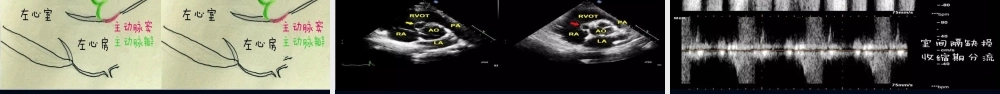

先天性心脏病:主动脉窦瘤破裂主讲人: 主动脉窦动脉瘤( aortic sinus aneurysm )是一种少见的先天性畸形,但在我国则并不太少。病人男性多于女性。本病是以右冠窦瘤常见,无冠窦瘤次之,左冠窦瘤少见。多为单个主动脉瘤受累。可破入临近腔室,多破入右心室,其次右心房、破入左心系统、肺动脉、心包腔等部位的罕见。本病常伴有室间隔缺损,主动脉瓣脱垂,主动脉瓣畸形等。基本概述 主动脉窦瘤大多系先天性畸形,仅少数为后天性病因所致,由梅毒、感染性心内膜炎、动脉硬化、主动脉夹层、创伤及医源性损害等原因破坏窦壁组织引起。主动脉窦瘤以男性多见,东方人群发病率相对较高。 主动脉根部有三个主动脉窦,即冠状动脉窦,根据冠状动脉起源的不同分别命名为右冠窦、左冠窦和无冠窦,其中无冠窦没有冠状动脉起源。右冠窦邻近右侧房室沟和右室流出道,左冠窦邻近左心房和肺动脉根部,无冠窦邻近右心房和左心房病因病理及血流动力学述 主动脉窦瘤( aortic sinus aneurysm )是指由于主动脉窦壁发育薄弱,主动脉中层弹力纤维缺乏,在主动脉高压血流的长期冲击作用下,形成向外膨出的囊状或瘤样病变。 主动脉窦瘤是一种少见的心血管畸形,大多系先天性畸形,仅少数为后天性病因所致。窦瘤未破裂时不引起血流动力学变化,患者多无明显症状及体征。窦瘤破裂常于剧烈活动、感染、分娩、外伤、心导管检查、情绪激动等情况下发生,起病急骤,表现为突发心前区剧痛、心慌、胸闷甚至晕厥等症状,因迅速出现大量左向右分流,以及伴发的主动脉瓣反流,从而引起心腔容量和心肌工作量突然增加,导致急性心力衰竭;主动脉内脉压增大,可导致冠脉供血不足;如果窦瘤破入心包,可引起心包填塞甚至死亡。 主动脉窦瘤一旦破裂,病情凶险,应尽早明确诊断和及时治疗。因超声心动图技术能无创、快速、准确地诊断此病,已成为临床首选的检查方法。概述主动脉窦与周围房室腔之间的关系。R. 右冠窦; L. 左冠窦; N. 无冠窦; LA. 左心房; RA. 右心房; RVOT. 右室流出道; PA. 肺动脉胸骨旁左心长轴切面。显示右冠窦呈囊袋样突入右心室,瘤壁可见回声中断心底短轴切面。显示右冠窦呈囊袋样突入右心室,瘤壁可见回声中断(箭头所指处)。 R. 右冠窦; L. 左冠窦; N. 无冠窦;LA. 左心房; RA. 右心房; RV. 右心室心底短轴切面。显示右冠窦呈囊袋样突入右心房,瘤壁可见回声中断(箭头所指处)。 R. 右冠窦; L....